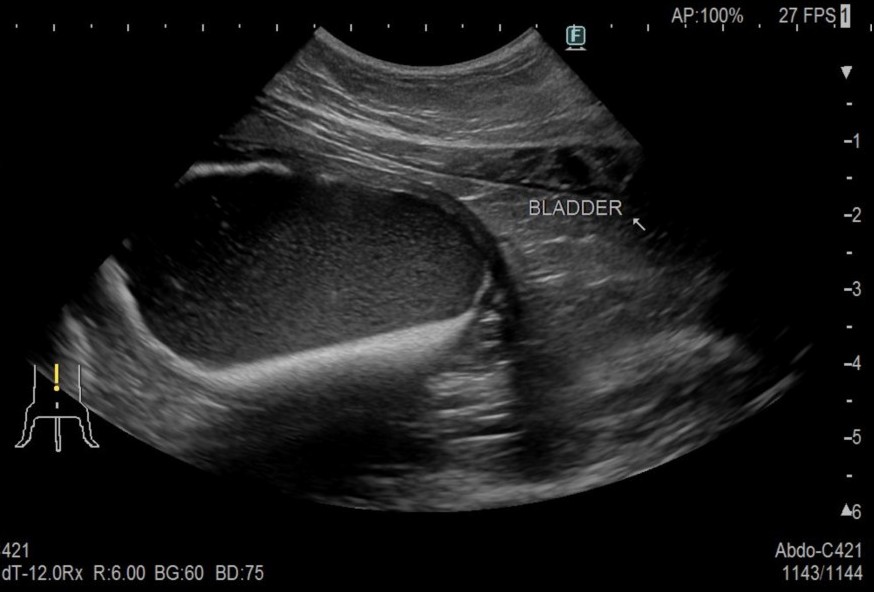

腹部触診にて固く拡張した膀胱を触知

レントゲンとエコー検査にて膀胱内に砂粒の存在と尿道の閉塞を確認

before